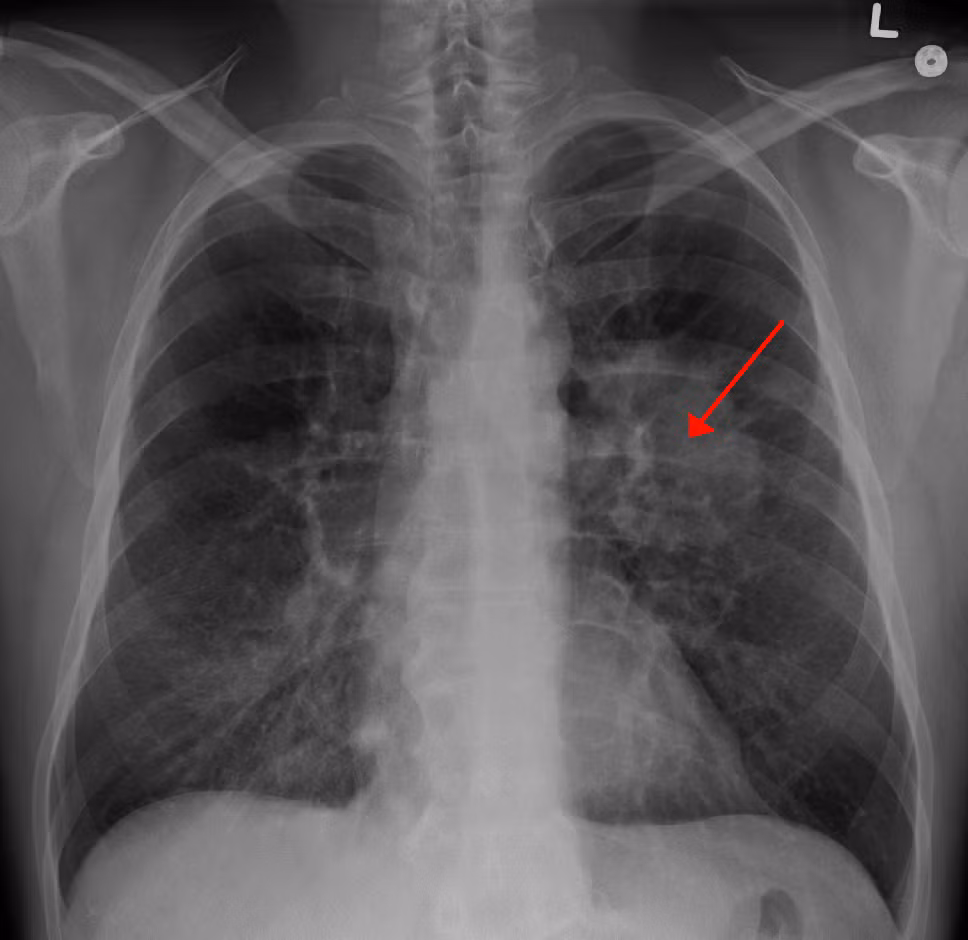

Theo đó, Dịch vụ Y tế Quốc gia Anh (NHS) kêu gọi những người có các triệu chứng như ho dai dẳng kéo dài hãy đi khám sớm, bởi theo các chuyên gia y tế, việc phát hiện bệnh sớm giúp ích cho quá trình điều trị bất cứ loại ung thư nào. Ảnh: Wikipedia.

Đặc biệt là bệnh ung thư phổi rất khó phát hiện trong giai đoạn đầu. Ảnh: SCC.